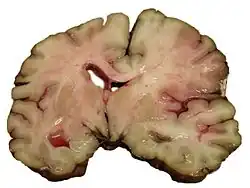

Traumatic brain injury: Sedation, ICP monitoring and management, Decompressive Craniectomy, Hyperosmolar therapy and maintain hemodynamic stability.